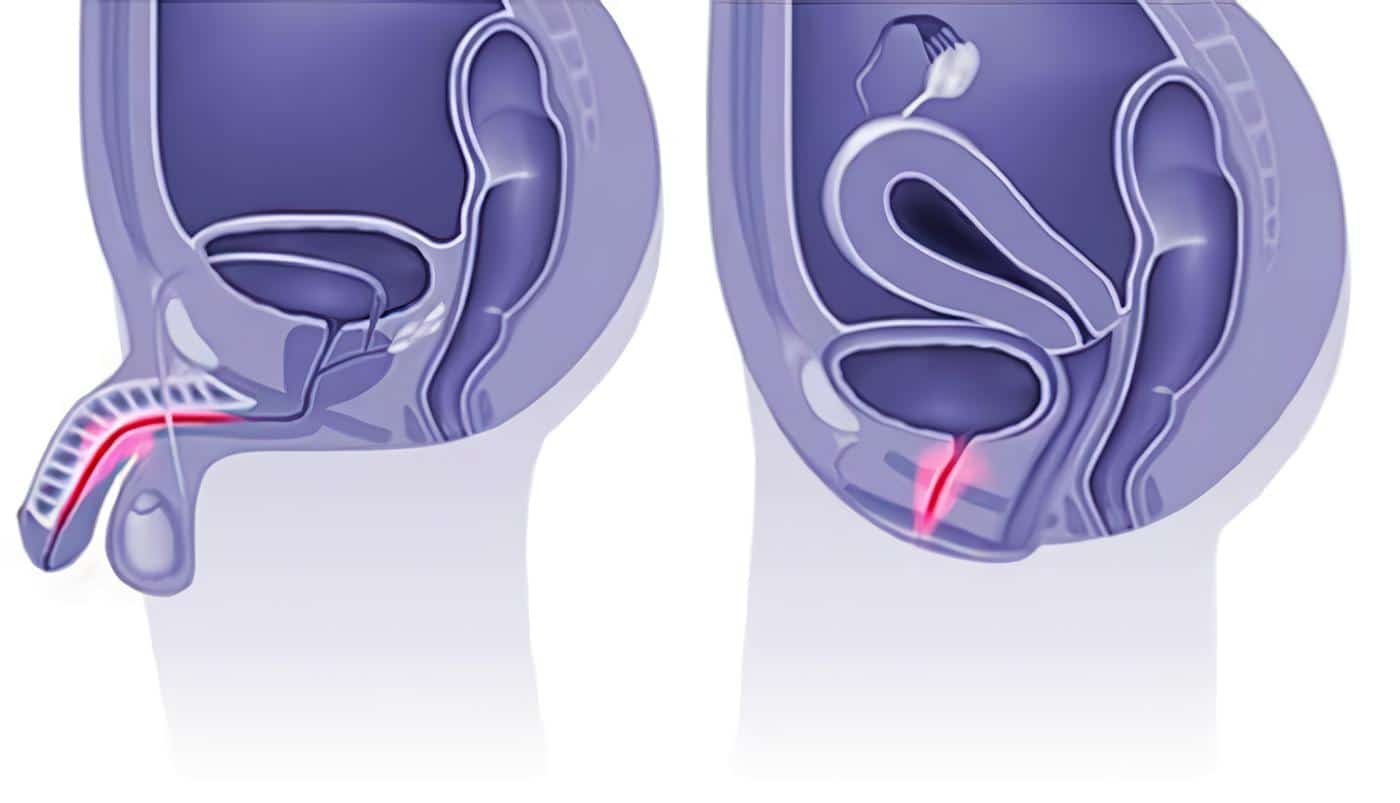

- El pene y el corazón son estructuras vasculares de similares características sometidos a los mismos factores de riesgo

- Lo que subyace en la DE es la enfermedad cardiovascular y el riesgo de morir